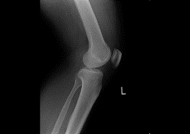

| 膝 | 手関節 | 足関節 |